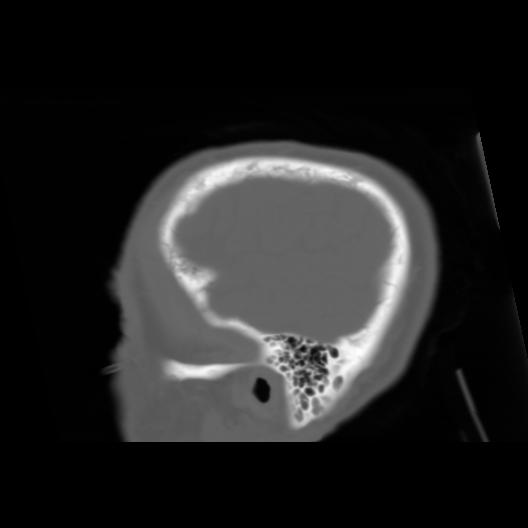

6 CEREBRO,,Sagittal,3.000,CEREBRO,Sagittal,